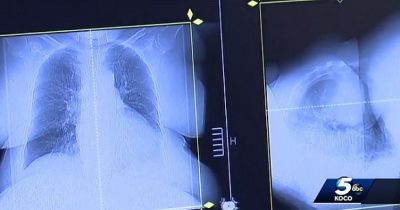

في يناير (كانن الثاني) 2017، كان جو تيبنس واثقاً من موته قريباً بسرطان الرئة لكن طبيباً بيطرياً اقترح عليه الاستعانة بعقار “فينبيندازول”، وهو مركب مضاد للديدان يستخدم لعلاج الديدان الخطافية والمستديرة وغيرها من الطفيليات المعوية لدى الحيوانات، خاصةً الكلاب.

وتناول حبوب علاج الكلاب، لكنه لم يخبر طبيبه بذلك، وأظهرت فحوصات خضع لها في سبتمبر (أيلول) 2017 تحسناً كبيراً في حالته.

وفي يناير(كانون الثاني) 2018، خضع تيبس لمسح نهائي لكشف تطور مرضه، وكانت المفاجأة شفي تماماً من السرطان.